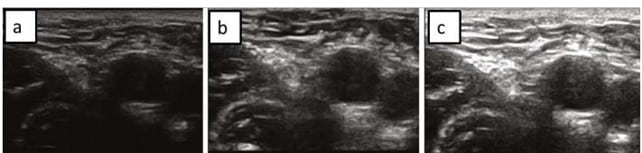

Por tanto, podemos diferenciar entre:

- Ganancia muy baja: Existe poco contraste entre estructuras por lo que no se puede apreciar con claridad las estructuras sobre las que incidir.

- Ganancia muy alta: La imagen es demasiado ecogénica apreciándose con dificultad y con artefactos el interior de los vasos. Además, los tejidos superficiales resultan demasiado “brillantes” dificultándose la visualización del paso de la aguja.

- Ganancia adecuada: Permite la distinción de los músculos respecto a las paredes vasculares, con facilidad para visualizar tejidos superiores, y el paso de la aguja en su inserción.